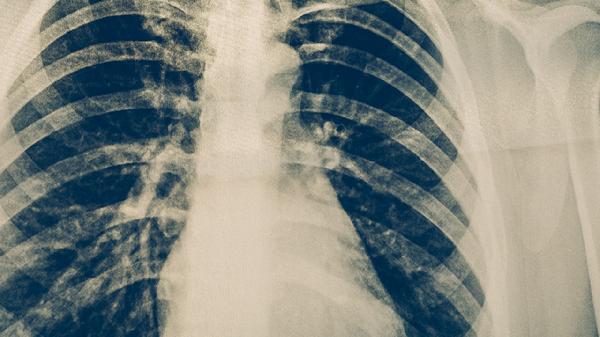

CT检查肺癌的准确率较高,是临床常用的筛查和诊断手段之一。CT能清晰显示肺部微小病灶,对早期肺癌的检出率明显优于胸片,但确诊仍需结合病理活检。

低剂量螺旋CT是目前肺癌筛查的首选方法,可发现直径小至2-3毫米的肺结节。对于实性结节,CT诊断准确率可达80%以上,能有效区分良恶性病变特征,如分叶征、毛刺征等。薄层CT扫描结合三维重建技术,可提高对磨玻璃结节的检出率,这类结节可能是早期肺腺癌的表现。增强CT还能通过观察病灶血供情况辅助判断性质,恶性结节多呈不均匀强化。

CT检查存在一定假阳性率,约15%-30%的肺结节最终病理证实为良性。炎症、结核、真菌感染等均可形成类似肺癌的影像表现。对于8毫米以下的非实性结节,CT难以准确判断性质。部分特殊类型肺癌如类癌、黏液腺癌的CT特征不典型,易与肺炎混淆。肺门及纵隔淋巴结转移的判断准确率约为70%,存在一定误差。